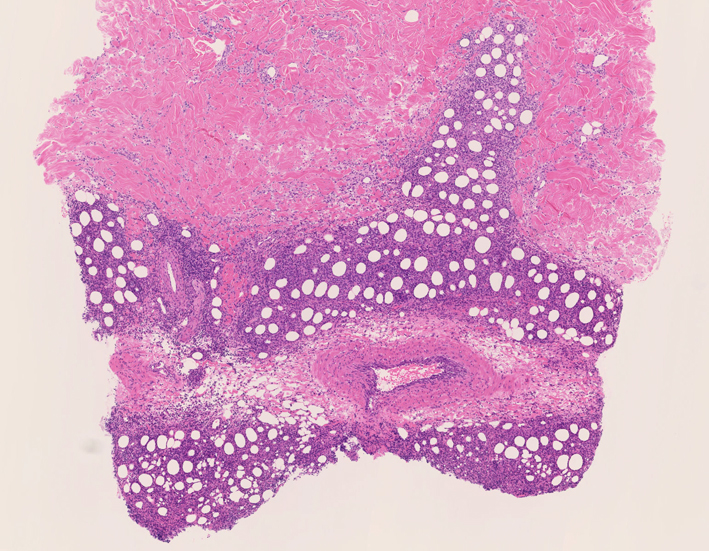

リンパ腫の定義: SPTCLは成熟細胞障害性T細胞(cytotoxic T-cell)由来で、皮下組織に脂肪識炎に似た組織像を呈しながら増殖する悪性リンパ腫。

皮下組織に優位な, 小~中型 Tリンパ球の密な浸潤が特徴。ときに大型リンパ球や組織球が混在する。 リンパ球の異型は, わずかなものから明瞭な異型を示す症例までさまざまである。